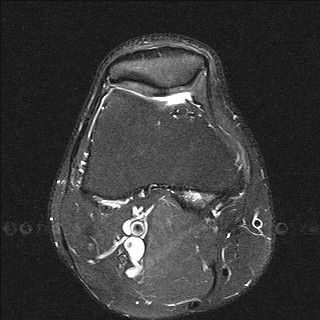

Дистрофические изменения суставного хряща надколенника (с использованием опции «картирования хряща»)